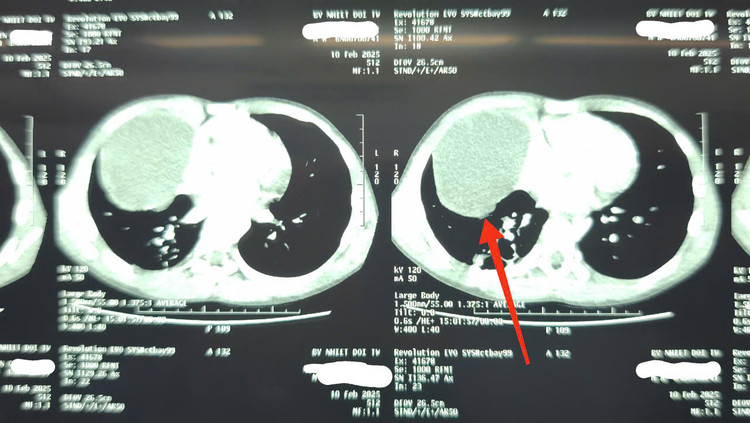

Tại khoa Nhi, kết quả kiểm tra khiến gia đình vô cùng bất ngờ: cháu B đau vùng mạn sườn phải, khó thở nhẹ, hình ảnh X-quang cho thấy trắng xóa 1/2 dưới vùng ngực phải, siêu âm có tràn dịch màng phổi và có hình ảnh của nang dịch. Chụp cắt lớp vi tính phát hiện xẹp phổi dạng dải thùy dưới phổi phải, có nang dịch trung thất trước kích thước 72x80mm.

| Khối u nang bì trung thất ở phổi bệnh nhi - Ảnh BVCC |